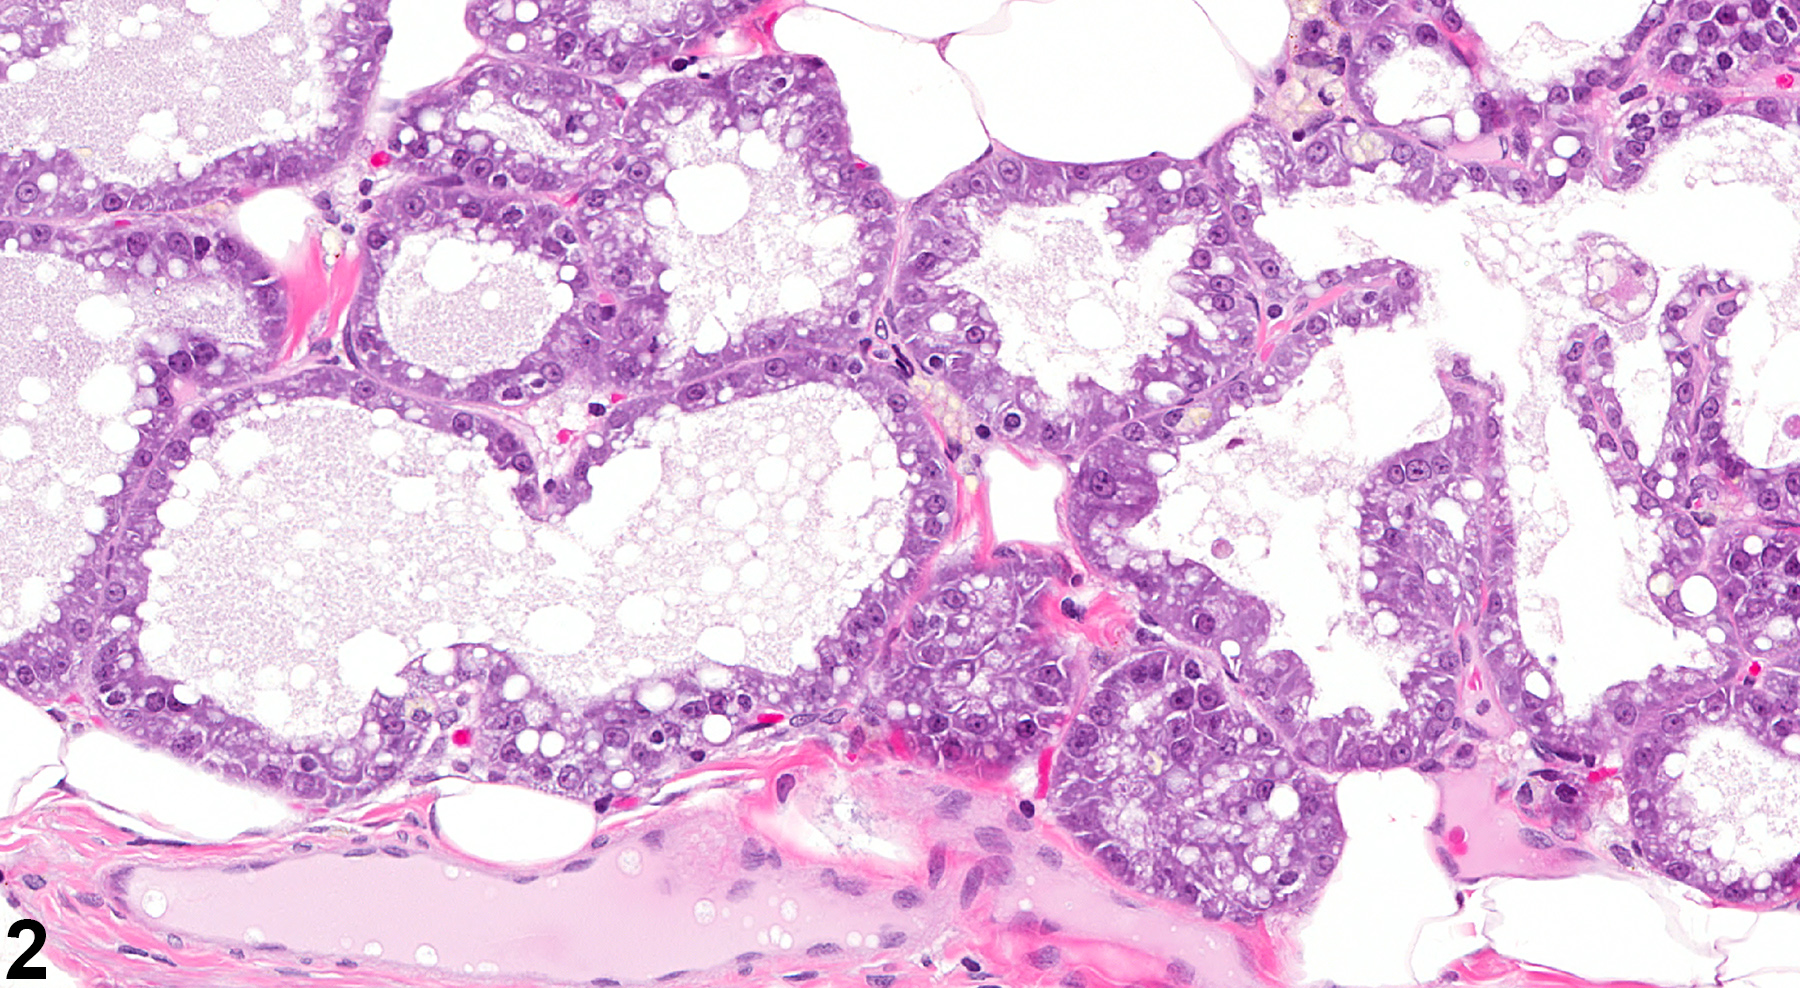

Atypical hyperplasia is sometimes observed (Figure 1 and Figure 2). This finding can occur in ducts, ductules, alveoli, or even within areas of lobular hyperplasia. It is characterized by lining cells arranged in multiple layers, infoldings, solid nests, or even papillary formations. The affected cells are pleomorphic and often enlarged, with features such as large hyperchromatic nuclei, increased numbers of mitotic figures, and increased cytoplasmic eosinophilia or basophilia. The cells with increased cytoplasmic eosinophilia often contain vacuoles that are suggestive of secretory cells, while the cells with the more basophilic cytoplasm most often do not have vacuoles and are suggestive of ductular epithelium. The alveoli may be normal in shape, or they may be irregular and enlarged. In contrast, proliferating cells of non-atypical hyperplasia lack the cellular atypia, architectural distortion, and other cytological abnormalities seen in atypical hyperplasia. Studies of chemically induced mammary cancer suggest a possible link between atypical ductular hyperplasia and adenocarcinoma (Harvell, et al.).

Mammary gland, Alveolus - Atypical Hyperplasia, in a female F344/N rat from a chronic study. There is a focal area of Atypical Hyperplasia (arrow) in the mammary gland.